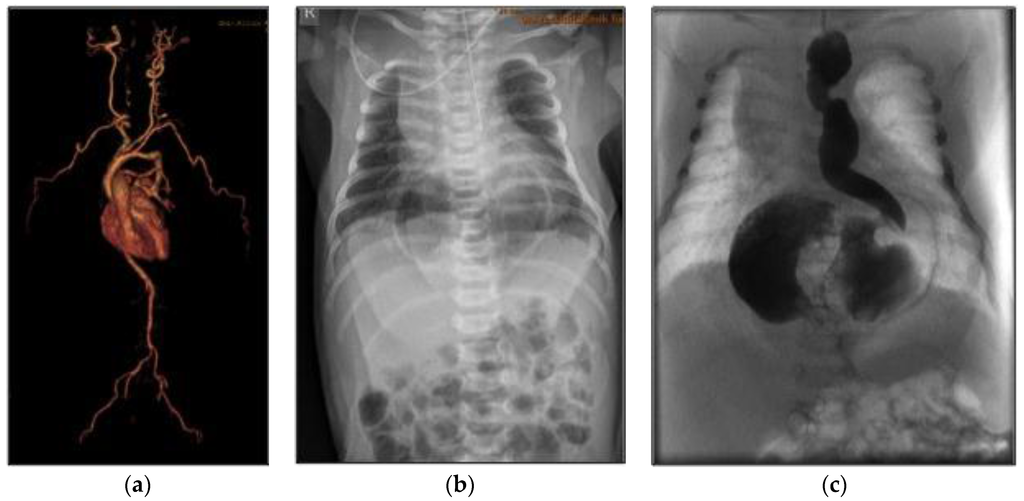

2. Case Report